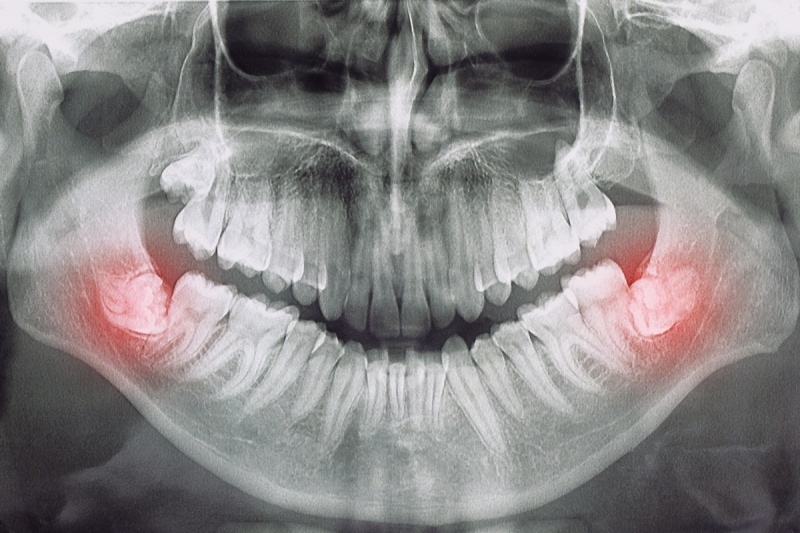

Wisdom teeth can become impacted, meaning they are trapped under the gum or bone and cannot fully emerge. This can cause pain, infection, and damage to neighbouring teeth.

A dentist or oral surgeon will take X-rays /CBCT (3d scan) to assess the position and development of the wisdom teeth. They will determine the best course of action, whether it’s a simple extraction or a surgical removal.